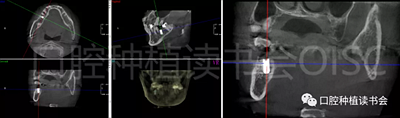

術(shù)前CBCT(美亞光電)檢查:47根分叉下方骨高度及骨寬度滿足即刻種植要求(圖13)。

圖13 47根分叉區(qū)骨寬度及骨高度(與下頜神經(jīng)管之間的距離)滿足即刻種植要求。

5.3.6 術(shù)后即刻CBCT(美亞光電)檢查種植體軸向及深度良好(圖19)。

圖19 術(shù)后即刻CBCT確認(rèn)種植體頰、

舌側(cè)骨板完整,并保持了足夠的厚度。